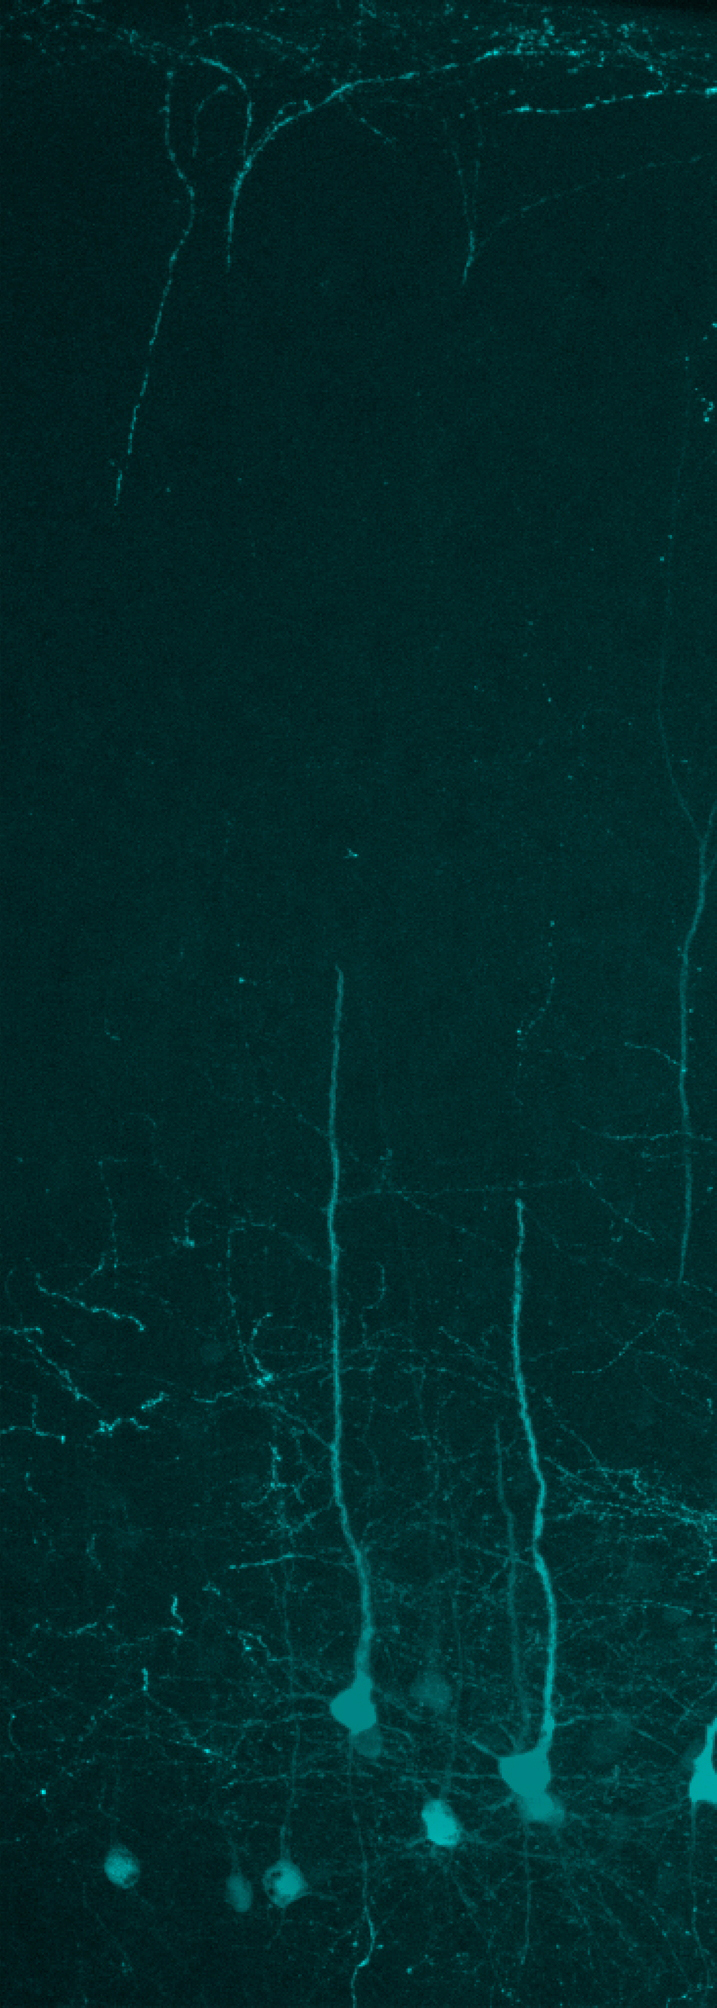

Wenn möglich, werden Ergebnisse ohne Versuchstiere mit Hilfe von Alternativmethoden gewonnen. Nicht-invasive Verfahren haben jedoch meist nur eine geringe Auflösung. So lassen sich die komplexen Interaktionen von Nervenzellen untereinander und mit ihrer Umgebung, sowie ihr Einfluss auf Verhalten meist nur mit Hilfe eigens dafür gezüchteter Versuchstiere klären. Neue Methoden und das verbesserte Wissen ermöglichen es heute wichtige Erkenntnisse zum Beispiel auch durch Studien an Fliegen zu gewinnen. An Hunden, Katzen oder Affen wird an den Instituten nicht geforscht.